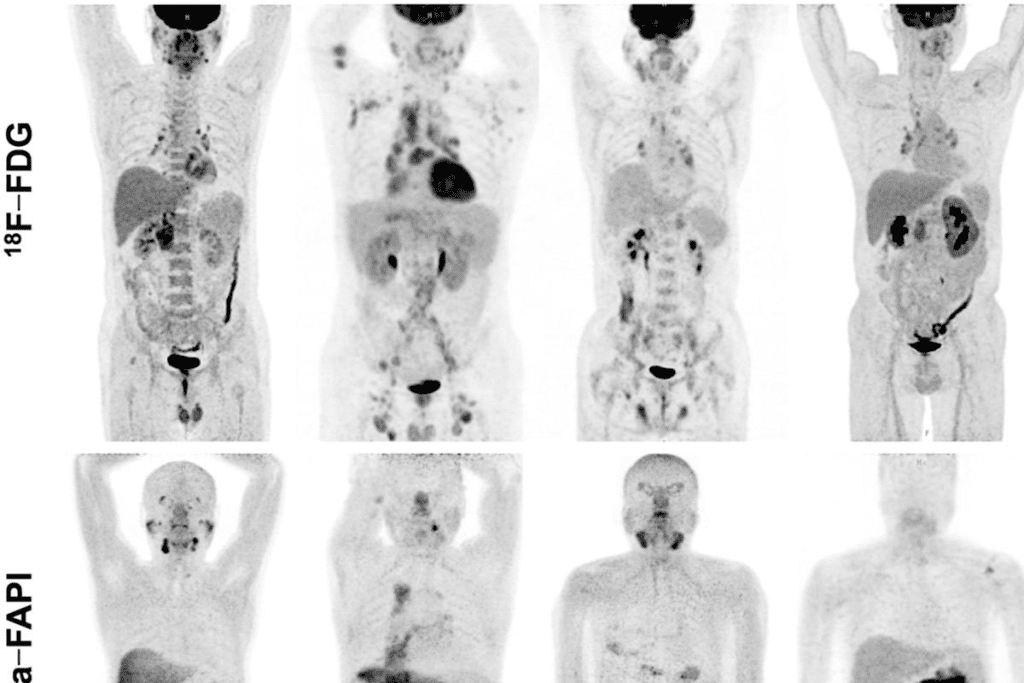

Color Interpretation in PET Imaging

PET scans use colors to show how active cells are. Bright colors mean cells are very active, often a sign of cancer. Knowing this color scale is key for correct diagnosis.

The colors range from black (low activity) to white (high activity). There are also shades of gray and other colors, depending on the tracer used.

Why Some Areas Appear Dark or Black

Dark or black spots on PET scans mean low cell activity. This can be because of:

• Normal tissue with low metabolic rate

• Benign conditions

• Certain types of cancer that don’t show high activity